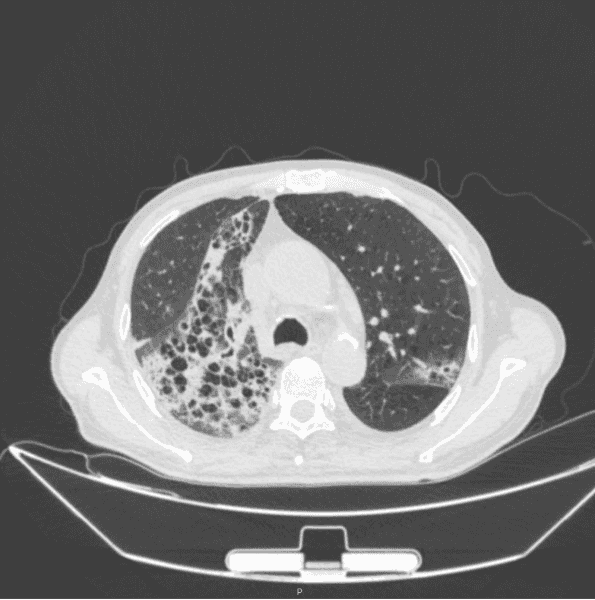

入院第六天我们通过 mNGS 检测出患者的血液和痰液中存在羊流产衣原体,可确认为肺炎的病原体但是由于衣原体感染大多都是混合感染,因此我们并没有停止帕拉西林钠他唑巴坦钠的使用在治疗第 10 天,我们复查了胸部 CT,结果示两肺间质性炎症较前改善,两肺少量胸腔积液(图 2)。

图 2:入院第十天胸部 CT,两肺间质性炎症较前改善,两肺少量胸腔积液患者因为检测出了乙肝小三阳和梅毒特异性抗体阳性,因此患者转院前往传染病医院进一步治疗,嘱患者出院后口服莫西沙星和克拉霉素抗感染治疗我们在患者出院二十天后进行随访。